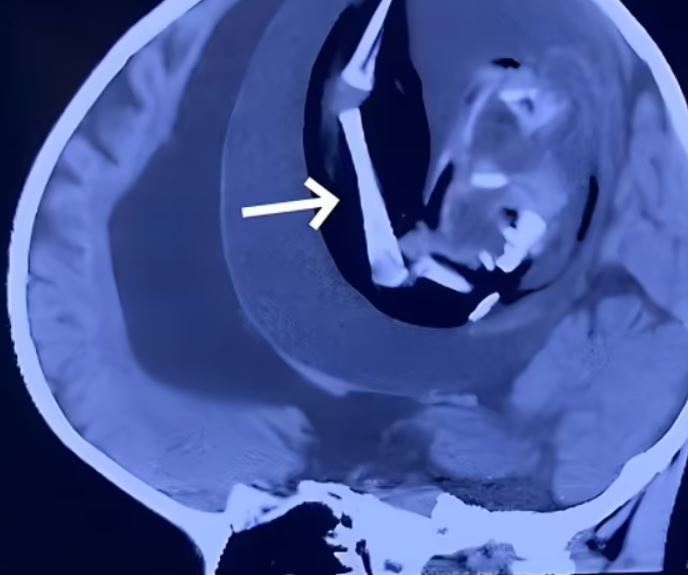

و أجرى الأطباء فحصًا بالمسح على رأس الطفلة، واكتشفوا وجود كتلة في جمجمتها يبلغ قطرها 13 سم، وهي أكبر قليلًا من كرة البيسبول، ولاحظ الأطباء وجود داخل طويلة من العظام داخل الكتلة.

و قرر الأطباء في تلك المرحلة إجراء عملية جراحية لمحاولة إزالة الكتلة وحلال العملية عثروا على كيس رحمي يحتوي على سائل بني سميك وجنين غير ناضج داخل جمجمة الطفلة.

كان للجنين عمود فقري وعظام ومايشبه الفم وعينين وشعر وساعدين ويدين وقدمين وكان طوله 18 سنتيمترا، وسببت تلك الحالة ضغط شديد على أنسجة مخ الطفلة، والتي كانت تصارع الموت بعد إصابتها بحالات من الصرع وظلت على قيد الحياة تحت أجهزة الإنعاش بينما كان يعاني من نوبات صرع بعد العملية الجراحية.